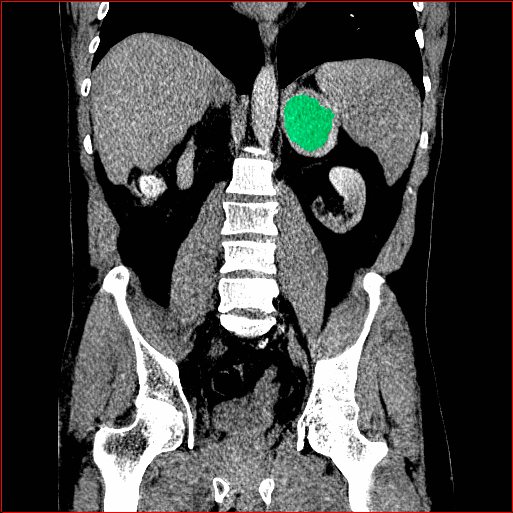

Figure 3 shows the generalizability of MAISI-v2 ControlNet for different body regions and voxel sizes. Figure 4 shows qualitative results for MAISI-v2 ControlNet on 5 types of tumors.

Figure 3: MAISI-v2 segmentation-guided results for small to large volume size and three different regions.

Liver Tumor

0.75×0.75×0.50.75\times 0.75\times 0.5

mm

512×512×768512\times 512\times 768

Figure 4: MAISI-v2 segmentation-guided results for five types of tumors. We show results for different voxel spacing and volume size to demonstrate the flexibility of MAISI-v2. Different Hounsfield Unit window is used to better show the contrast between tumor and normal tissues.